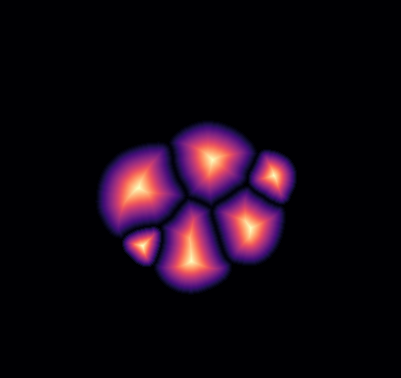

\text{Qualitative Results}